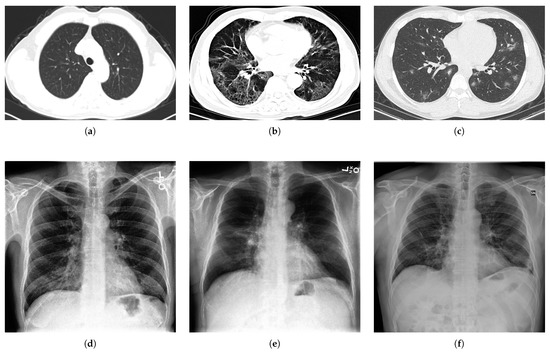

Regarding the CT scans, we have selected the COVIDx CT-2A dataset (It can be downloaded from: https://www.kaggle.com/hgunraj/covidxct (accessed on 20 May 2021), which has been constructed by collecting a number of open data sources [108,109] and comprises 194,922 CT slices from 3745 patients. The scans of the dataset are related to three classes: novel coronavirus pneumonia due to SARS-CoV-2 viral infection (NCP), common pneumonia (CP), and normal (N) controls (i.e., images from non-infected individuals). For NCP and CP CT volumes, slices marked as containing lung abnormalities were leveraged. Moreover, all the CT volumes contain the background, in order to avoid model biases. An example of a representative image for each image class is reported in the first row of Figure 2.

In order to stress the effectiveness of the proposed approach in view of numerical comparisons, which are presented later, for the CXRs, we found a highly imbalanced dataset that contains few COVID images. This is a representative of the actual situation of public datasets, and it has been selected “ad hoc” to check the effectiveness of the proposed approach with respect to the corresponding supervised state-of-the-art approaches based on deep learning, which usually need a large amount of well-balanced training data.

Specifically, for the CXRs, we have selected the COVID-XRay-5K dataset (It can be downloaded form: https://github.com/shervinmin/DeepCovid (accessed on 20 May 2021), which has been constructed by collecting data from two publicly available sources [15]. The downloadable COVID-Xray-5k dataset is already split in training and test sets, and it contains 2084 training and 3100 test images. However, from the web URL, it can be downloaded a training set composed of only 580 Non-COVID and 84 COVID images, respectively, while the test set is composed of 3000 Non-COVID and 100 COVID images. An example of a representative image for each class is reported in the second row of Figure 2.